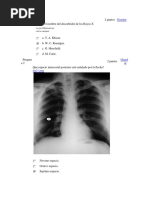

Test de

Mallampati

Se valora la visualización de

estructuras anatómicas faríngeas de

la vía aérea con el paciente en

posición sentada y la boca

completamente abierta y sin fonar.

De este modo se clasifica la vía

aérea como:

Clase I: visibilidad del paladar

blando, úvula y pilares amigdalinos,

Clase II: visibilidad del paladar

blando y úvula,

Clase III: visibilidad del paladar

blando base de la úvula,

Clase IV: imposibilidad para ver el

paladar blando.

¿Qué valora el test Mallampati?

a) Visualización de pared posterior de la faringe.

b) Cuerdas vocales.

c) Inmovilidad del cuello.

d) Distancia entre incisivos menor de 4 cm.

e) Distancia tiromentoniana mayor de 6.5 cm.